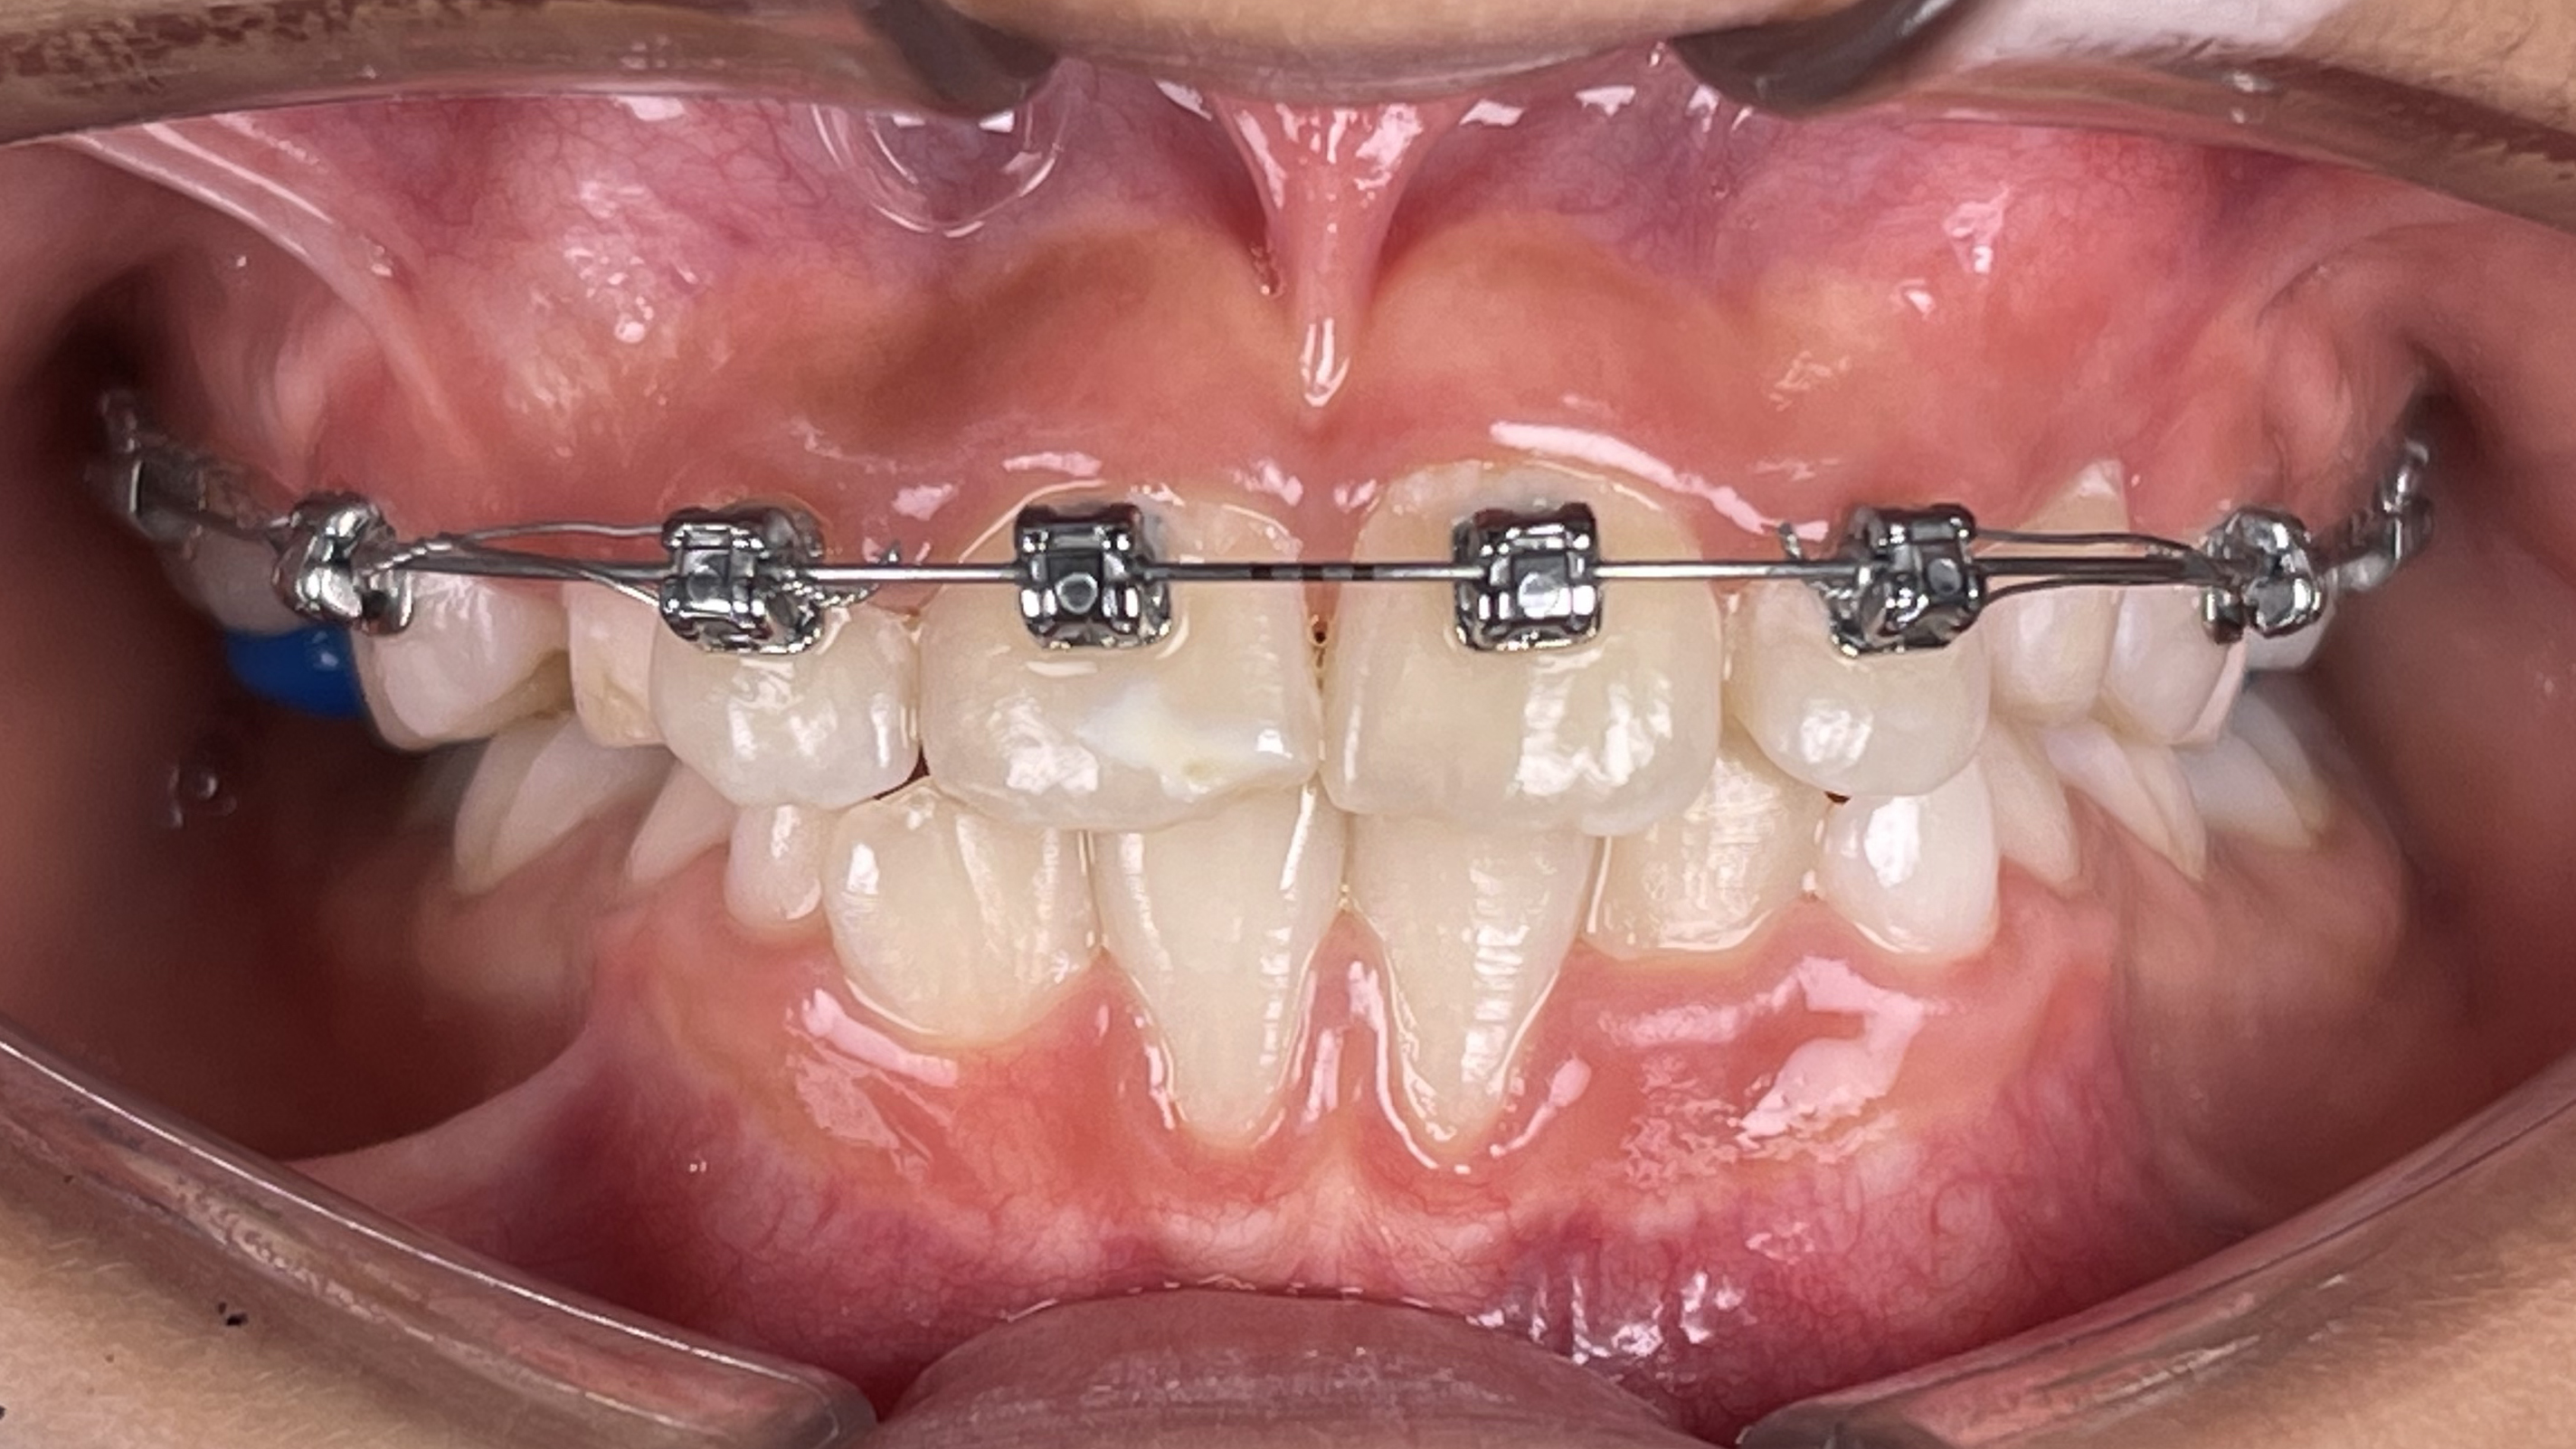

Smiles Gallery

We love to see our patients smile! Here are some of our best before-and-after pictures,

all in one fantastic Smile Gallery